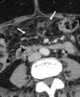

Diffuse metastatic disease

Disseminated disease refers to a diffuse disease-process, generally either infectious or neoplastic. The term may sometimes also characterize connective tissue disease. [Source: Wikipedia ]